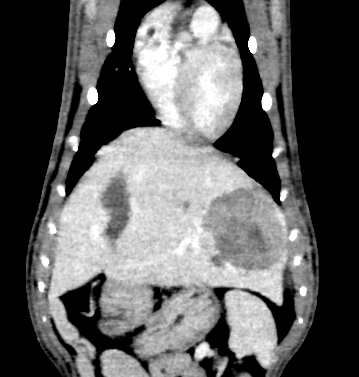

Bij Berry werd eerste een CT-scan uitgevoerd met contrast om de levermassa goed in beeld te brengen. Er werden ook degeneratieve veranderingen in de nieren en milde lymfadenomegalie vastgesteld.